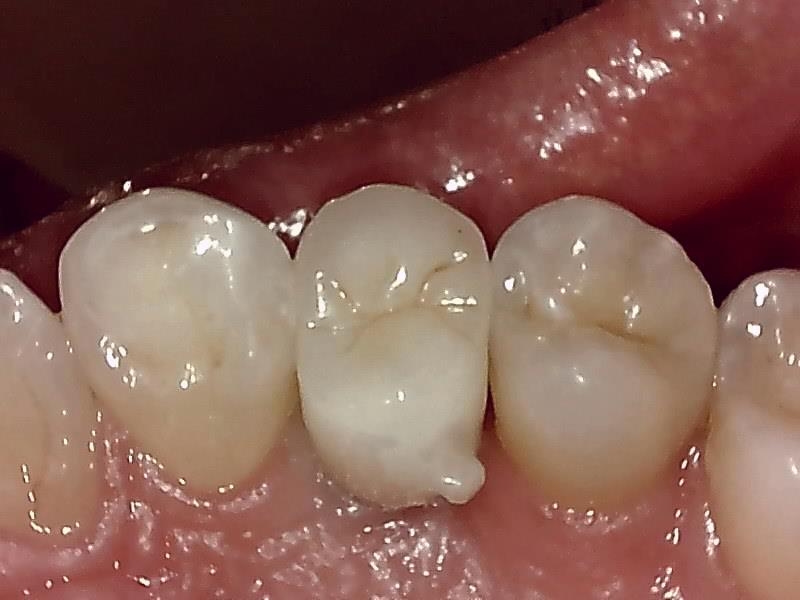

インプラント埋入した状態は良好です。

術前の時は瘦せていた顎堤が適切なグラフト手技により

しっかりした厚みのある顎堤が隆起している。

インプラント埋入後、10ヶ月経過した健全な顎堤の状態です。